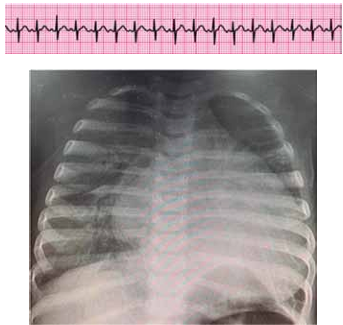

Lactente de 6 meses com tosse, coriza e desconforto respiratório progressivo há 2 dias (chega a ficar “roxinho” nos lábios quando mama, segundo a mãe). Nega internações ou problemas de saúde prévios. Foi trazido ao pronto-socorro devido a piora do desconforto, palidez cutânea e inapetência, com importante comprometimento do estado geral. Ao exame físico, está em mau estado geral, descorado +++/4+, extremidades frias, tempo de enchimento capilar de 5 segundos, pulsos finos, FC = 200 bpm, PA = 62 x 33 (43) mmHg, SatO2 = 87% em ar ambiente, FR = 68 ipm, ausculta pulmonar com estertores crepitantes em bases e ausculta cardíaca com bulhas rítmicas normofonéticas com sopro sistólico +/6+ em borda esternal esquerda. Obtido ritmo cardíaco e radiografia de tórax a seguir.

Enunciado 4584195-1

(Arquivo pessoal; imagens usadas com autorização)

Com base nos dados apresentados, assinale a alternativa que contenha a hipótese diagnóstica mais provável e a conduta mais adequada para o caso.